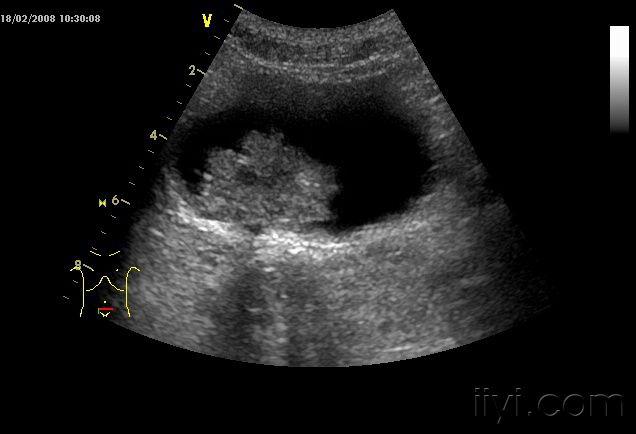

典型膀胱癌声像图一例

图片尺寸636x434